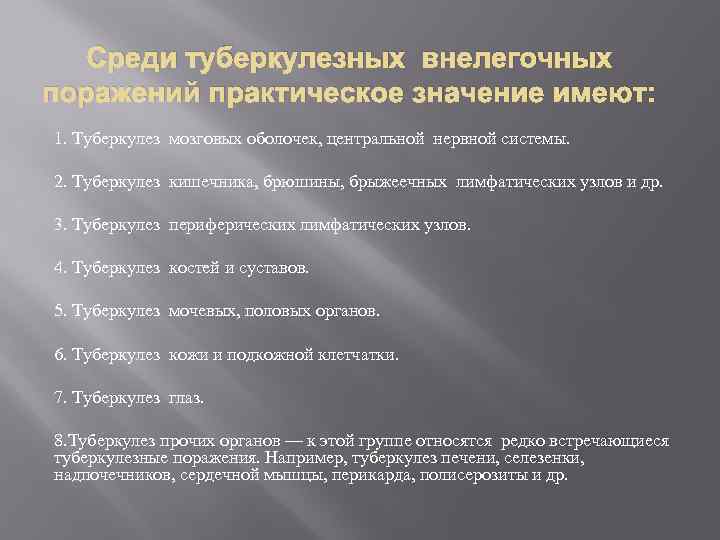

Среди туберкулезных внелегочных поражений практическое значение имеют: 1. Туберкулез мозговых оболочек, центральной нервной системы. 2. Туберкулез кишечника, брюшины, брыжеечных лимфатических узлов и др. 3. Туберкулез периферических лимфатических узлов. 4. Туберкулез костей и суставов. 5. Туберкулез мочевых, половых органов. 6. Туберкулез кожи и подкожной клетчатки. 7. Туберкулез глаз. 8. Туберкулез прочих органов — к этой группе относятся редко встречающиеся туберкулезные поражения. Например, туберкулез печени, селезенки, надпочечников, сердечной мышцы, перикарда, полисерозиты и др.

Среди туберкулезных внелегочных поражений практическое значение имеют: 1. Туберкулез мозговых оболочек, центральной нервной системы. 2. Туберкулез кишечника, брюшины, брыжеечных лимфатических узлов и др. 3. Туберкулез периферических лимфатических узлов. 4. Туберкулез костей и суставов. 5. Туберкулез мочевых, половых органов. 6. Туберкулез кожи и подкожной клетчатки. 7. Туберкулез глаз. 8. Туберкулез прочих органов — к этой группе относятся редко встречающиеся туберкулезные поражения. Например, туберкулез печени, селезенки, надпочечников, сердечной мышцы, перикарда, полисерозиты и др.